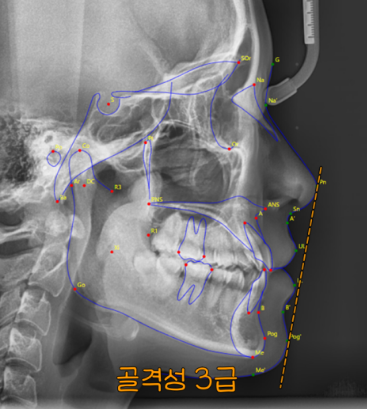

그로 인해,

코 끝과 턱끝을 이은 선이

입술이 후퇴되어 있습니다.

이러한 형태를

골격성 3급 부정교합 이라 하는데요.

이는 아래턱이 위턱보다

더 앞으로 자라 있는 상태로

정상 교합에서는 윗니가 아랫니를

자연스럽게 덮고 있어야 되지만,

이러한 문제가 있을 경우

아랫니가 윗니보다 앞으로 나와 있거나

위아랫니가 절단 및 반대 교합으로

맞물리게 됩니다.

이러한 교합은 저작 기능 뿐만 아니라

발음, 얼굴의 인상에도 영향을 주기 때문에

심미성과 기능 모두 고려한 접근이 필요합니다.